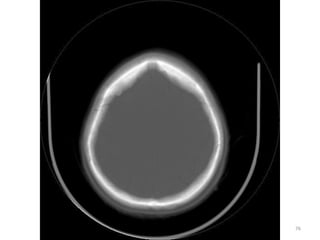

IMAGENS ÓSSEAS

83